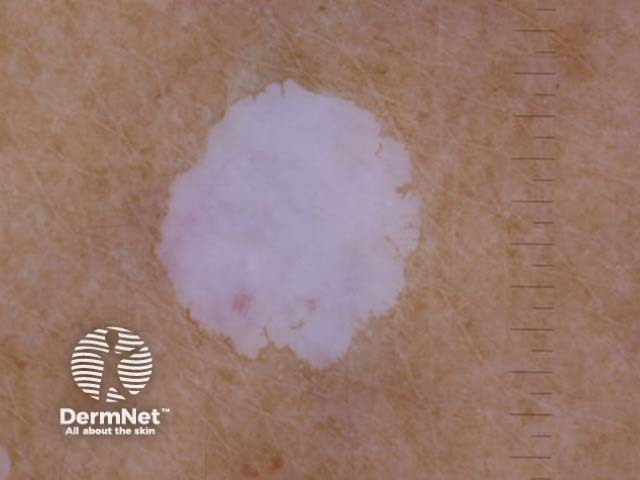

Idiopathic guttate hypomelanosis typically presents as smooth pale (hypopigmented) or white (depigmented) macules 2–5mm (range up to 1.5cm) in diameter most commonly on the sun-exposed aspects of the forearms, shins, and V of chest. Lesions are usually multiple and asymptomatic.

Porcelain-white patch extending peripherally

Macroscopic view